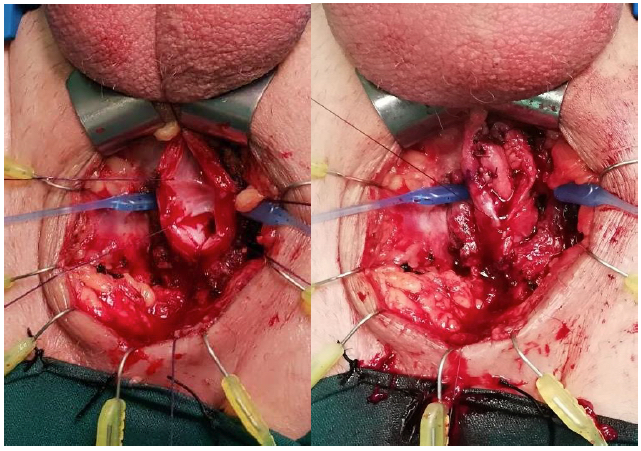

Aunque se ha descrito la colpocleisis parcial sin resección del trayecto fistuloso (técnica de Latzco), la técnica más utilizada es la resección de la fístula (Video 3). Después del posicionamiento en litotomía y la visualización de la fístula (Figura 21), se realiza una resección del tejido vaginal incluyendo el trayecto fistuloso (Figura 22). La vejiga se repara luego en dos planos invaginantes con material reabsorbible 3-0 o 4-0 (Figura 23) y posteriormente la vagina se cierra en un tercer plano con un material similar. Se puede interponer un colgajo de grasa de labio mayor con la técnica de Martius si se considera necesario, por ejemplo, en fístulas complejas (Figura 24).55

Reparación Abdominal

La técnica transvesical (de O’Connor) se basa en una cistotomía amplia desde el domo vesical hasta llegar a la fistula por posterior, con adecuada visualización y eventual cateterización de los uréteres (Figura 25). Se debe realizar una cuidadosa disección del plano vesicovaginal (Figura 26). Cierre de la pared vaginal con material reabsorbible 3-0 y luego cierre de la vejiga con similar sutura (Figura 27). Se puede además movilizar un colgajo de peritoneo o epiplón que se interpone entre ambas suturas.